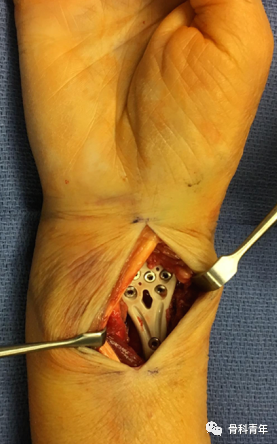

四、桡骨远端关节置换

关节置换用于严重关节内粉碎骨折的治疗已应用于肱骨近端骨折、肱骨远端骨折、胫骨平台骨折等。同理,关节置换也可用于桡骨远端骨折。适用于严重粉碎性、关节内、骨质疏松性骨折的一期治疗,或内固定失效的二期翻修。通常采用桡背侧切口,自第3/4间室间进入。